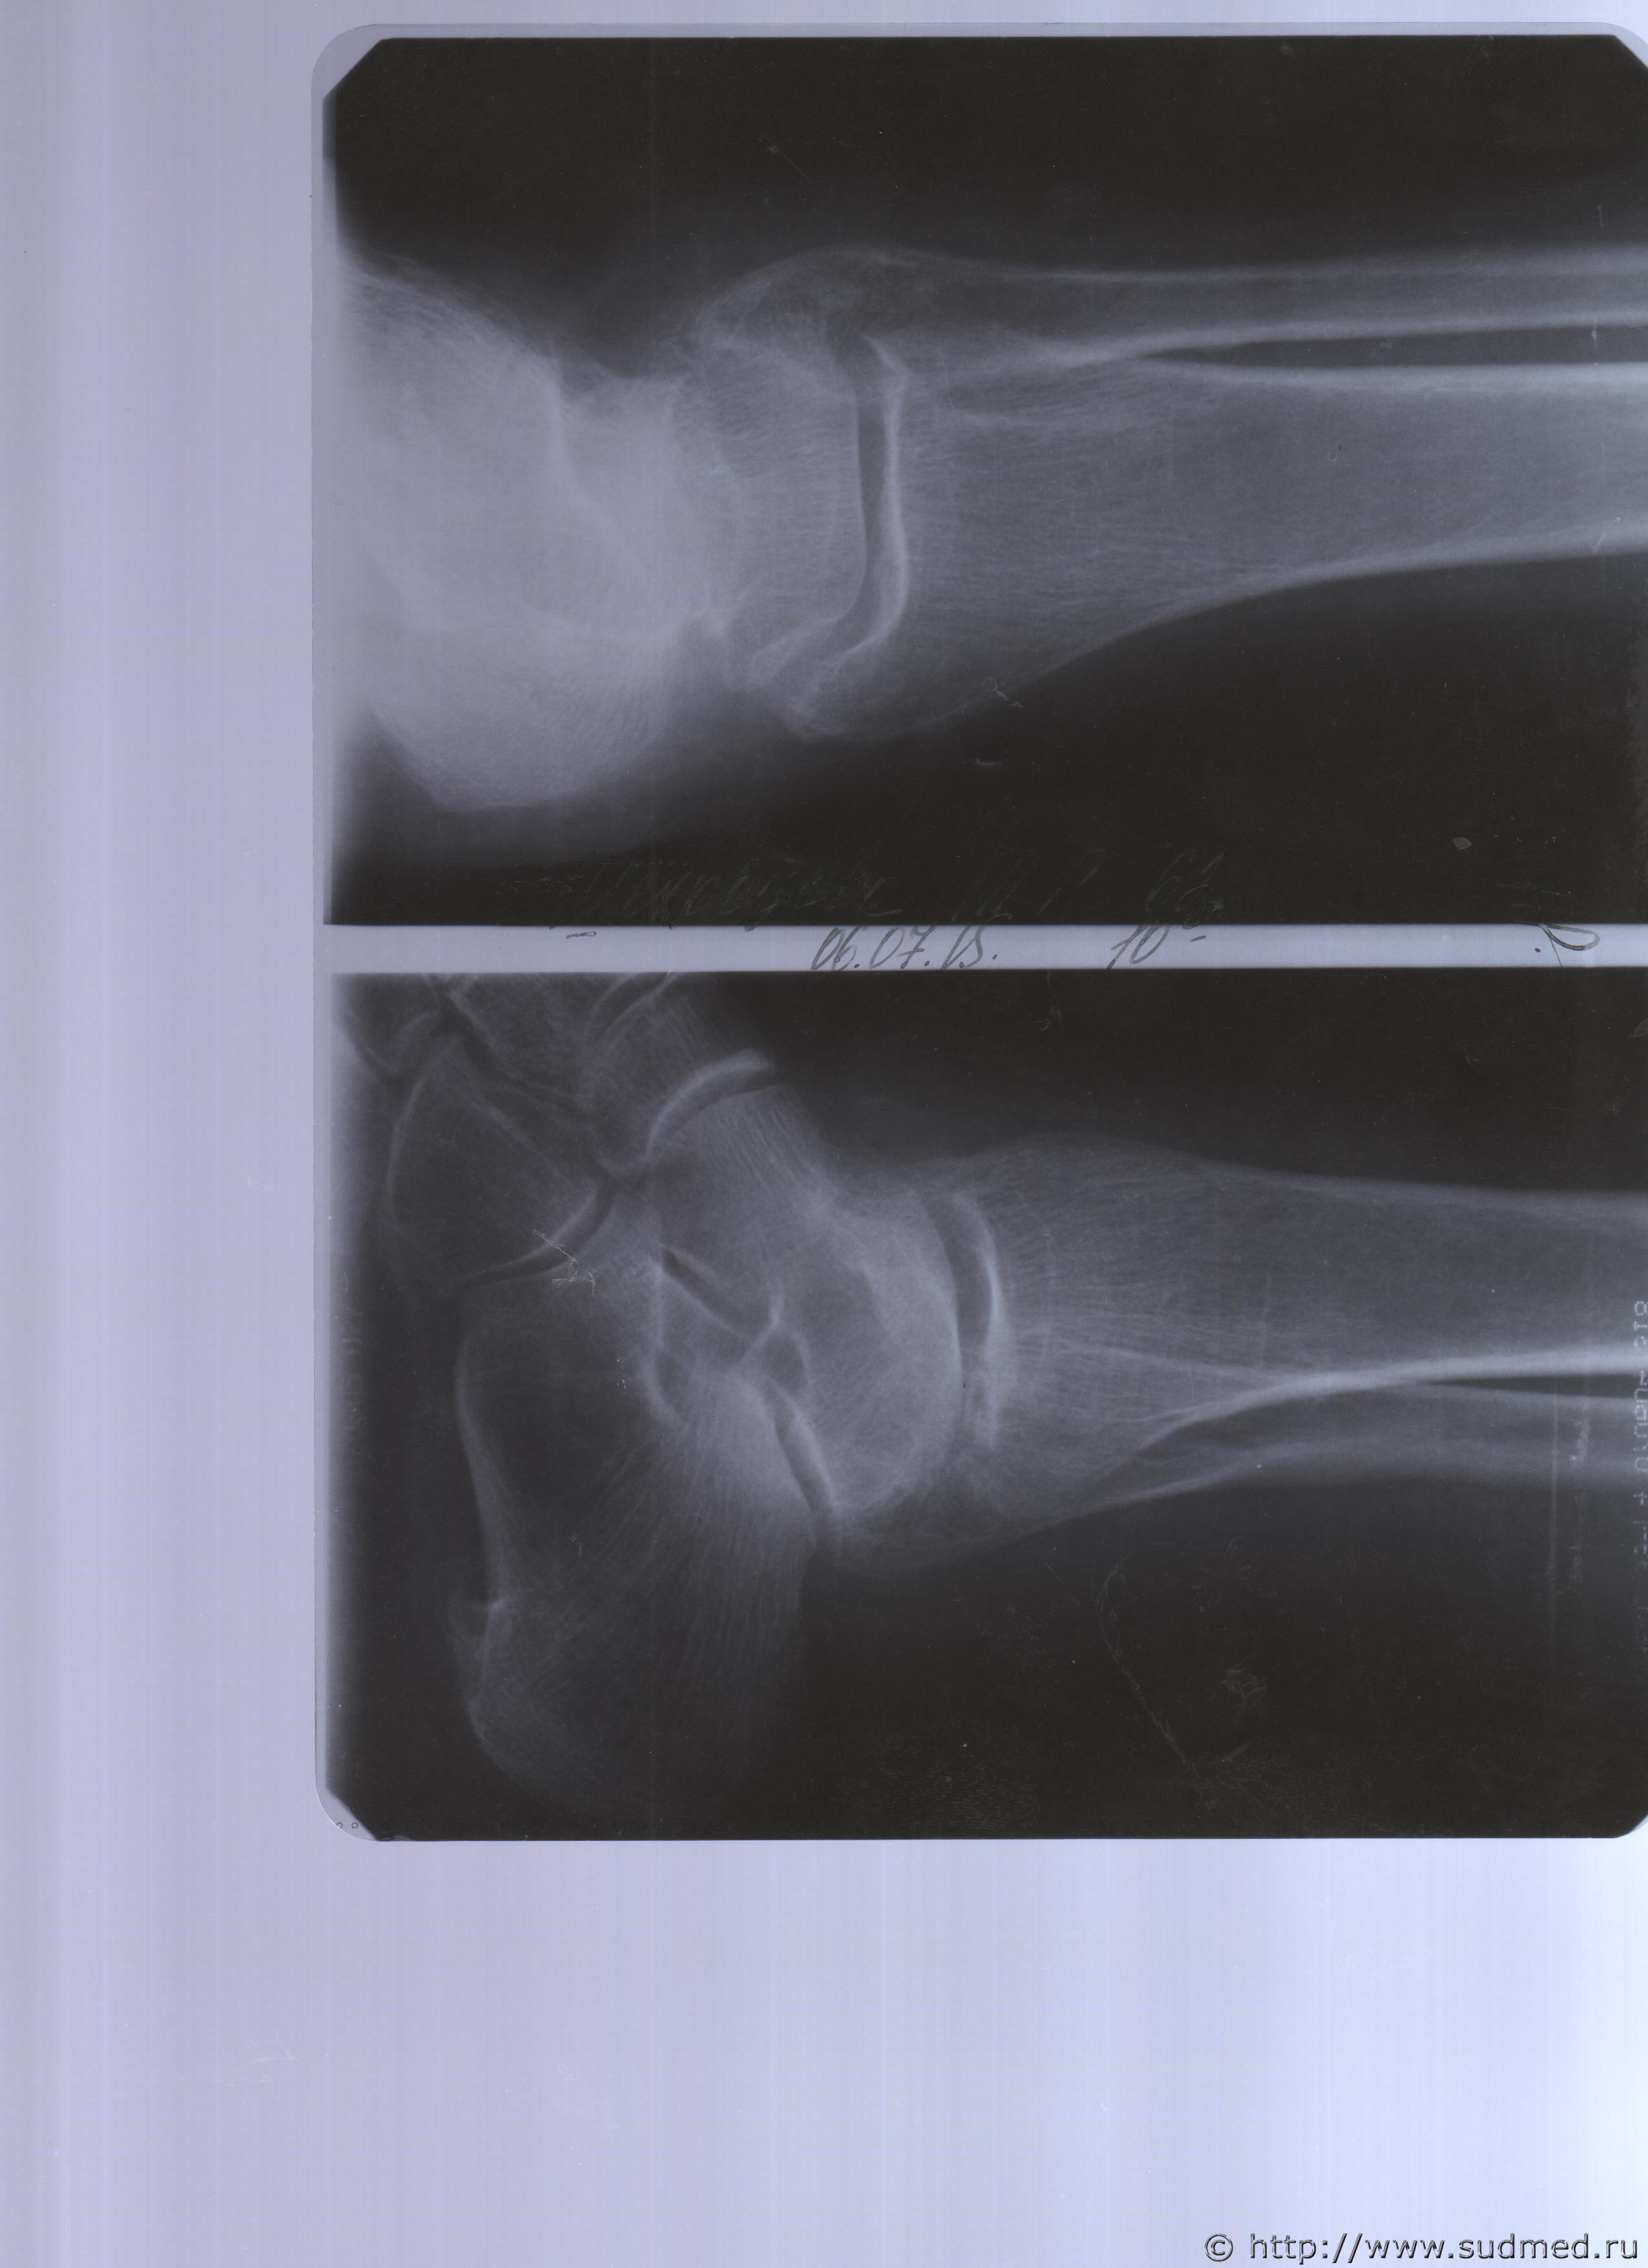

Радомир, большое спасибо за консультацию. Заключение судмедэксперта было на основании первого снимка от 06.07.2015 г. Это 1 и 2 снимок на форуме( дважды скопировала) по травме голени. Больше снимков на первое освидетельствование не было, а потом, почти через год в августе месяце 2016 года в СМЭ были представлены все имеющиеся в наличии снимки ( за 12 мес.) вместе с описаниями. Первое освидетельствование эксперт пишет, что невозможно определить время получения травмы, хотя на самом снимке есть запись от 06.07.2015 г. в 10.00 час.

Представляю еще раз первый снимок сделанный в день травмы. ( не знаю я сейчас открыла снимок. есть дата 06.07.2015г.)

Посмотрел и сравнил снимки области голеностопного сустава от 06.07.15г., от 04.08.15г., от 25.08.15г. Качество рентгенограмм весьма посредственное (рентгеновская аппаратура старая и условия исследования не оптимально подобраны). Опять же, оч.вероятно, что исследуя сами пленки можно сказать больше: анализ их фото на компьютере однозначно хуже, чем просмотр под лупой на негатоскопе.

На рентгенограмме в прямой проекции от 06.07.15г. в краеобразующей зоне по латеральной (наружной) поверхности нижней трети диафиза малоберцовой кости видна тонкая (шириной менее 1мм) линия перелома. Четкая, не завуалированная. Углы отломков не сглажены. Локальных изменений костной ткани в её окружности не наблюдается. Такой набор рентгенологических симптомов характерен для "свежих" костно-травматических изменений (примерно, в пределах от момента получения травмы до трех недель после получения перелома. Только по рентгенограммам точнее определить невозможно). Смещения отломков нет. В этой же проекции создается впечатление об изменениях в метадиафизарной зоне кости (примерно в месте перехода её диафиза-"трубчатой части" в лодыжку), их можно принять за "старый", сросшийся перелом. Если в экспертизе рентгенолог описал именно их, то его мнение вполне обосновано, однако, ему следовало также высказаться и по поводу изменений кости, о которых я написал выше (эксперт и консультант-рентгенолог их не заметили??? не придали значение???).

На последующих снимках (от августа) наблюдается незначительное смещение отломков (их стояние удовлетворительное, т.е. нет необходимости принимать каких-то специальных меры по улучшению их взаимного расположения). Хорошо видна формирующаяся костная мозоль в зоне перелома. Линия перелома завуалирована, широкая, прослеживается фрагментарно. Углы отломков сглажены, их края выраженно изменены (неравномерный остеопороз и остеосклероз). Это характерно для срастающегося (консолидирующегося) перелома и не противоречит предъявляемой дате травмы ("06.07.2015г.").

Так мне кажется по имеющимся изображениям. Возможно, рентгенолог, анализируя сами пленки, выявит что-то иное или дополнительное.